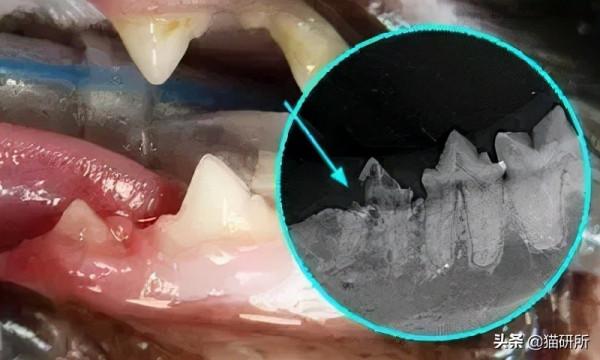

●牙片顯示有牙根吸收

牙根吸收 圖自:DeBowes L J, DuPont G A